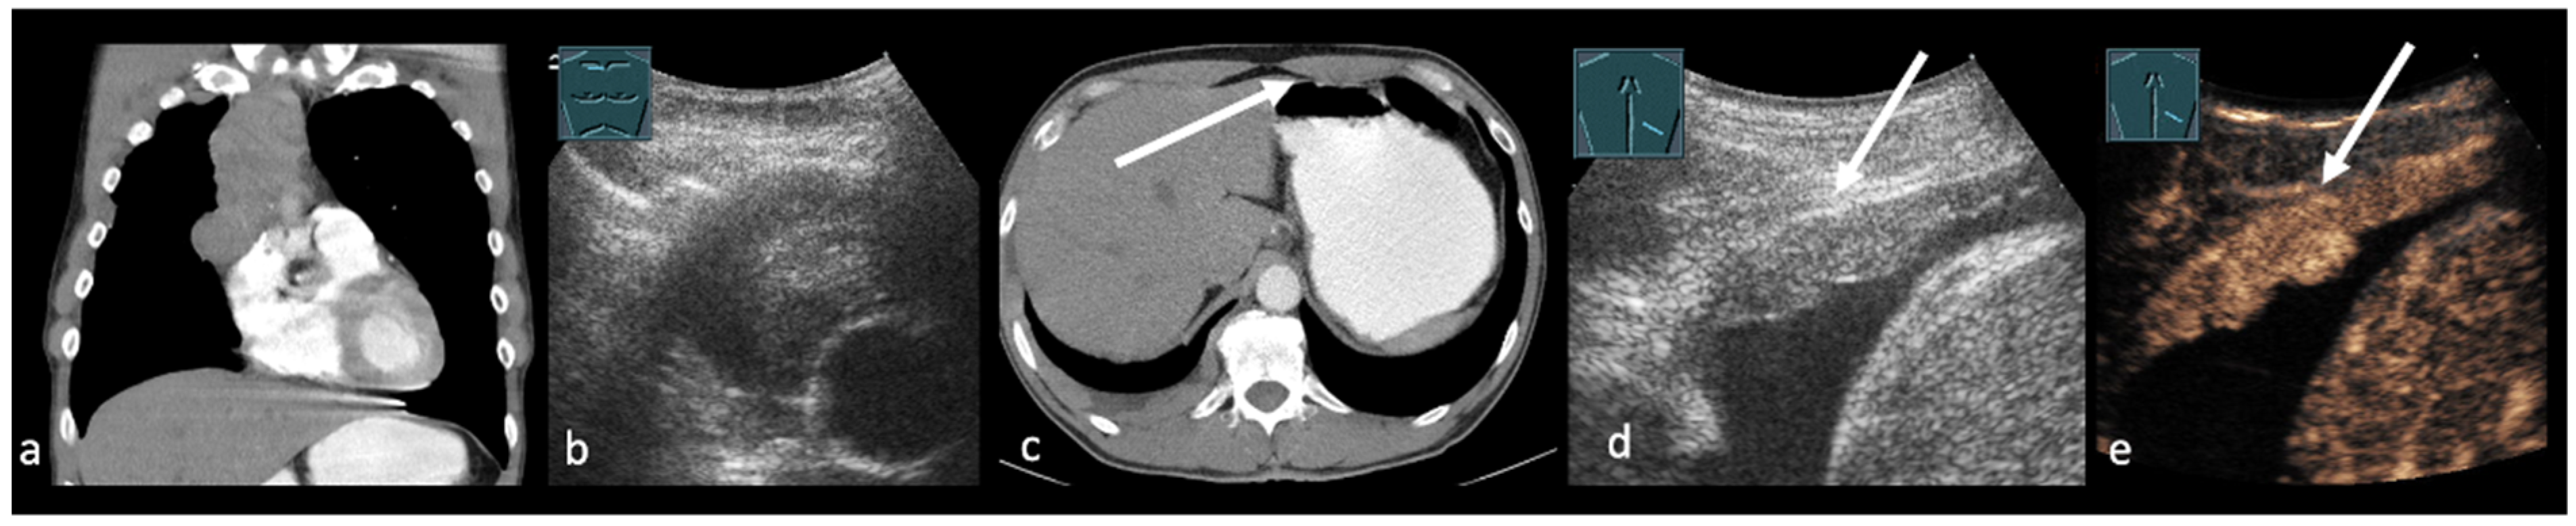

3. Transthoracic Ultrasound in the Evaluation and Characterizing of Local Tumor Size (T-Stage)

- Suzuki, N.; Saitoh, T.; Kitamura, S. Tumor invasion of the chest wall in lung cancer: Diagnosis with US. Radiology 1993, 187, 39–42. [Google Scholar] [CrossRef]

- Caroli, G.; Dell’Amore, A.; Cassanelli, N.; Dolci, G.; Pipitone, E.; Asadi, N.; Stella, F.; Bini, A. Accuracy of transthoracic ultrasound for the prediction of chest wall infiltration by lung cancer and of lung infiltration by chest wall tumours. Heart Lung Circ. 2015, 24, 1020–1026. [Google Scholar] [CrossRef] [PubMed]

- Bandi, V.; Lunn, W.; Ernst, A.; Eberhardt, R.; Hoffmann, H.; Herth, F.J.F. Ultrasound vs. CT in detecting chest wall invasion by tumor: A prospective study. Chest 2008, 133, 881–886. [Google Scholar] [CrossRef] [PubMed]

- Prosch, H.; Mathis, G.; Mostbeck, G.H. Percutaneous ultrasound in diagnosis and staging of lung cancer. Ultraschall Med. 2008, 29, 466–478. (In Japanese) [Google Scholar] [CrossRef] [PubMed]

- Findeisen, H.; Trenker, C.; Figiel, J.; Greene, B.H.; Görg, K.; Görg, C. Vascularization of Primary, Peripheral Lung Carcinoma in CEUS—A Retrospective Study (n = 89 Patients). Ultraschall Med. 2019, 40, 603–608. (In English) [Google Scholar] [CrossRef] [PubMed]

- Safai Zadeh, E.; Huber, K.P.; Görg, C.; Prosch, H.; Findeisen, H. The Value of Contrast-Enhanced Ultrasound (CEUS) in the Evaluation of Central Lung Cancer with Obstructive Atelectasis. Diagnostics 2024, 14, 1051. [Google Scholar] [CrossRef]